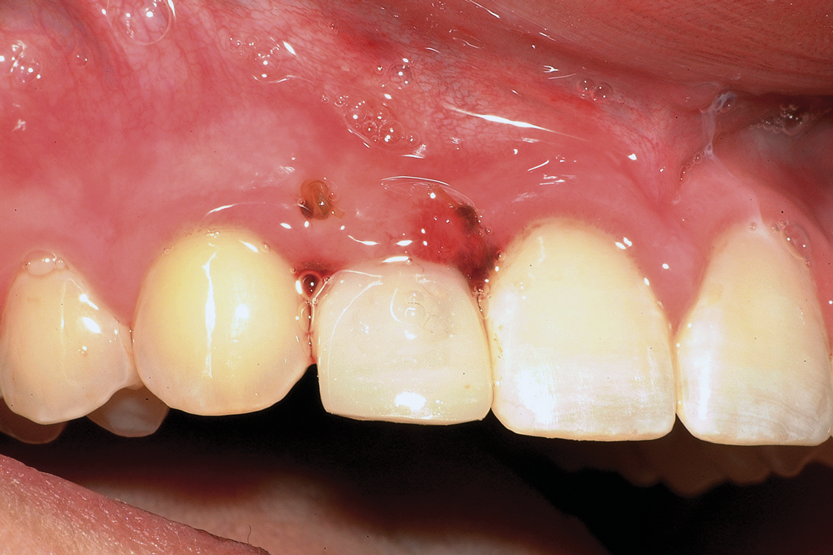

Fig 5. Ankylosed tooth No. 9 due to trauma in a 13-year-old patient.

Figure 5

Fig 6. Radiograph illustrating resorption of tooth No. 9 and 75% root maturation on tooth No. 20 (mandibular left second premolar) prior to autotransplantation.

Figure 6

Fig 7. Six weeks postoperative, after autotransplantation of tooth No. 20 into site No. 9.

Figure 7

A less commonly used but highly effective method of replacing lost anterior teeth is autotransplantation.18 A common indication for autotransplantation is the replacement of a missing maxillary anterior tooth with a mandibular second premolar. (A case example is shown in Figure 5 through Figure 10.) Timing of the surgery is critical. Orthodontic treatment must be timed so that the recipient site is ready when the donor tooth has two-thirds to three-fourths root development. Measurements must be made to ensure that the crown width of the donor tooth is comparable to the contralateral incisor of the tooth being replaced.

A socket is surgically created in the recipient site, and the donor tooth is atraumatically extracted; the entire dental follicle must be intact and undamaged. The donor tooth is placed in the newly created socket. There must be no pressure on the periodontal ligament, and the transplanted tooth must be out of occlusion. The tooth is stabilized for 6 weeks with a light orthodontic wire. As the tooth matures, it may erupt normally; however, orthodontic treatment is frequently required to move the tooth into the correct position for restoration.